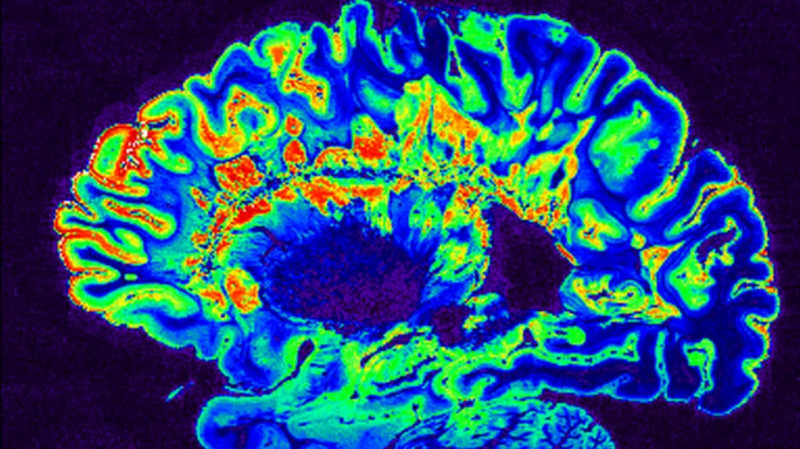

Čeští vědci vedení Milanem Němým z ČVUT využívají umělou inteligenci k odhalování drobných problémů v mozku, které mohou předcházet rozvoji duševních onemocnění, jako je Alzheimerova choroba. Pomocí moderních metod magnetické rezonance (MRI) se zaměřují na zachycení jemných změn v mozkových strukturách a jejich propojení, které nelze snadno vidět. #UměláInteligence #VýzkumMozku #AlzheimerovaChoroba